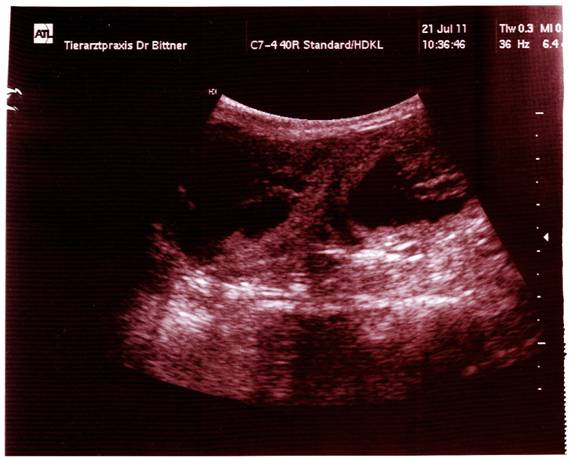

21.07.2011  |

:  |

MiniFee  |

hatte heute ihren Ultraschall-Termin …

… und der Tierarzt hat 3

Babys ganz klar erkannt. Ich

bin happy, dass MiniFee tragend ist und es ihr

& ihren Baby’s gut geht !!!  |